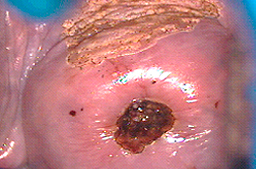

Cuando se utiliza en vagina, vulva y pene puede dar una profundidad mayor de la deseada y ocasionar problemas de cicatrización como se observa en las imágenes, o perforaciones del tejido hacia vejiga y/o recto.